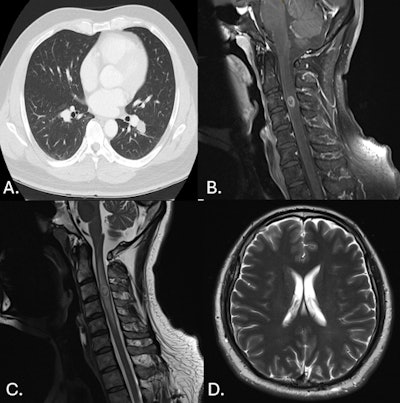

41-year-old man. (A.) CT Chest axial: peribronchovascular lesions within the superior segment of the left upper lobe. (B.) MR C Spine sagittal T1 contrast fat sat: round lesion at the level of C3 with peripheral hyperintensity. (C.) MR C Spine sagittal T2: thick-walled lesion at the level of C3 within the cervical spine with central hyperintensity. (D.) MR Brain axial T2: small lesion of the left frontal lobe that is hyperintense with leptomeningeal enhancement. There is also associated mild cortical edema.